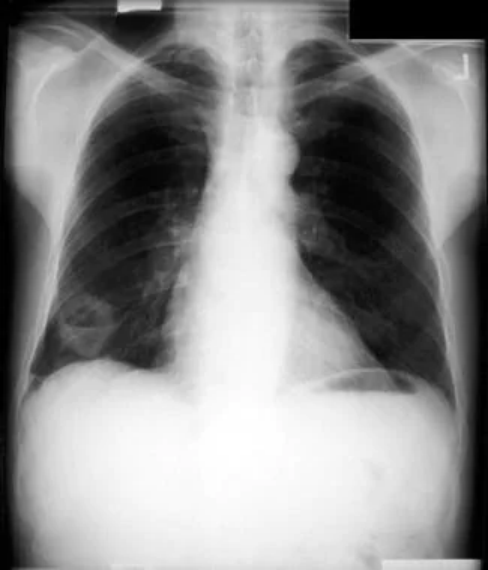

非小细胞肺癌。左下叶非小细胞癌继发的左胸腔积液和容量减少。对胸腔积液取样,发现是恶性的。因此,病变无法手术。